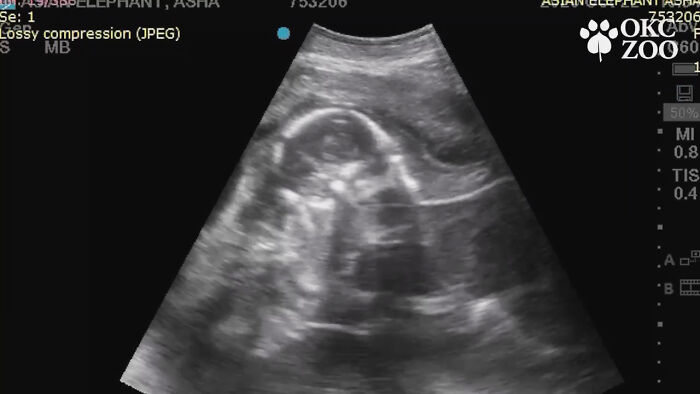

Enter Asha the female elephant and her recently published baby ultrasound that’s been circulating the internet. The explanatory video was posted by the Oklahoma City Zoo, with whom Bored Panda got in touch for an interview, and people find it both cute and fascinating.

A video of Asha’s ultrasound was published last week on the Oklahoma City Zoo and Botanical Garden’s Facebook page, stating the expected birth due day and that she’s already eight months into her 22-month pregnancy (around 660 days).

The video caption read “A tiny trunk and little legs? This ultrasound is ultra-sweet! The Oklahoma City Zoo is thankful for 25-year-old Asha’s growing Asian elephant calf, due in February 2022.” They also took the opportunity to wish everyone a great thanksgiving.

Ultrasounds are a regular procedure to check on the elephant’s pregnancy and are conducted by the zoo’s veterinary team. The most recent ultrasound—the one seen in the video—concluded that both the mother and the baby are as healthy as they can be.

Unlike with human baby ultrasounds, which are often very hard to decipher, this one is surprisingly clear. The head, the trunk, and the legs are all vivid and easy to see, but the video also points out these parts for good measure.